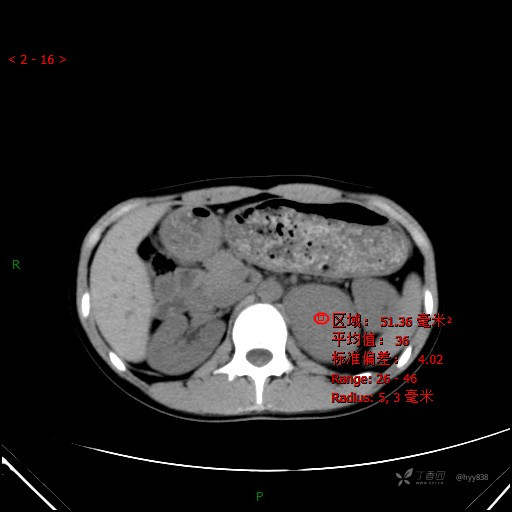

CT值